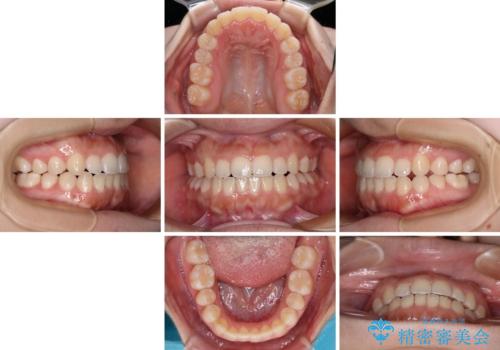

- 上下前歯のクロスバイトと叢生を気にして来院された患者様です。

インビザラインでの治療を希望されていて、デコボコの程度が中等度であり、安価なパッケージにて対応可能と判断されたため、インビザライン・モデレートを用いて矯正治療を行うこととしました。